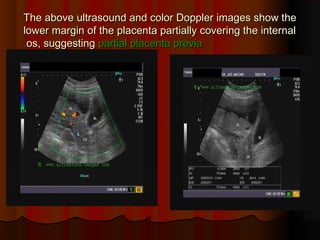

The above ultrasound and color Doppler images show theThe above ultrasound and color Doppler images show the

lower margin of the placenta partially covering the internallower margin of the placenta partially covering the internal

os, suggestingos, suggesting partial placenta previapartial placenta previa..

The above ultrasoundand color Doppler images show theThe above ultrasound and color Doppler images show the lower margin of the placenta partially covering the internallower margin of the placenta partially covering the internal os, suggestingos, suggesting partial placenta previapartial placenta previa..